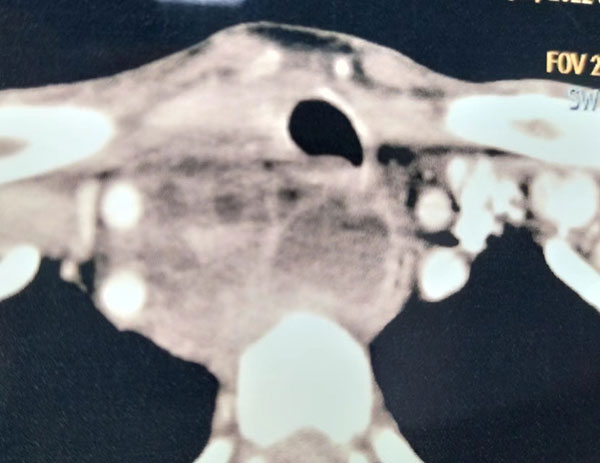

患者,男,73岁,咽喉疼痛、吞咽困难4天为主述就诊,体温达40°C,体质瘦弱,精神萎靡,步态蹒跚,颈部外观无明显红肿,CT显示,颈深部巨大脓肿,推压食管及气管移位,向下延及纵膈主动脉弓上缘。以往经验,病人很难救治。花费高,成功率低,潜在纠纷可能性大。病案讨论,有人力主送上级。

孙志强主任医师综合大家意见,病人的信任是我们工作最大动力,救病人于危重时是三甲医院应有的担当。与病人及家属充分沟通后,制定出较为完善的治疗方案,邀请胸外科赵呈华副主任一同上台,成功完成脓肿切开,植管引流,每日两次冲洗。半月后痊愈出院。病人家属送上锦旗,表示感谢。